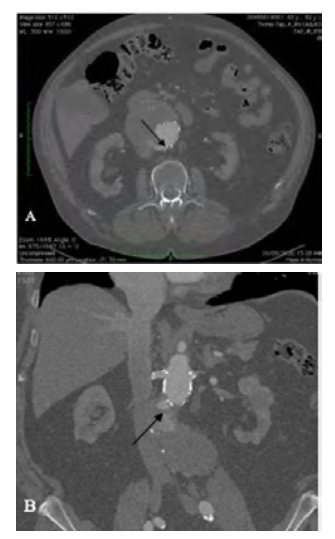

The patient did not attend the next appointment after hospital discharge, and he was lost for follow-up. Three years after the initial EVAR, a CTA scan was performed showing a delayed type Ia endoleak secondary to aortic neck dilatation with significant growth of the aneurysm sac, with a maximum diameter of 9.8 cm (Figures 1 and 2). The patient remained asymptomatic.